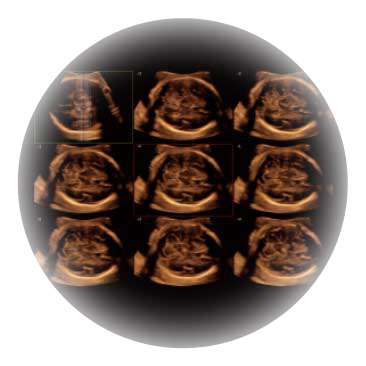

自动获取标准切面,自动完成测量,帮助医生快速完成检查,同时提升测量准确性。

宽频带腹部凸阵探头和腹部容积探头、大角度腔内探头和腔内容积探头、独特的生殖专用曲柄探头,为妇产应用提供全面诊疗方案。